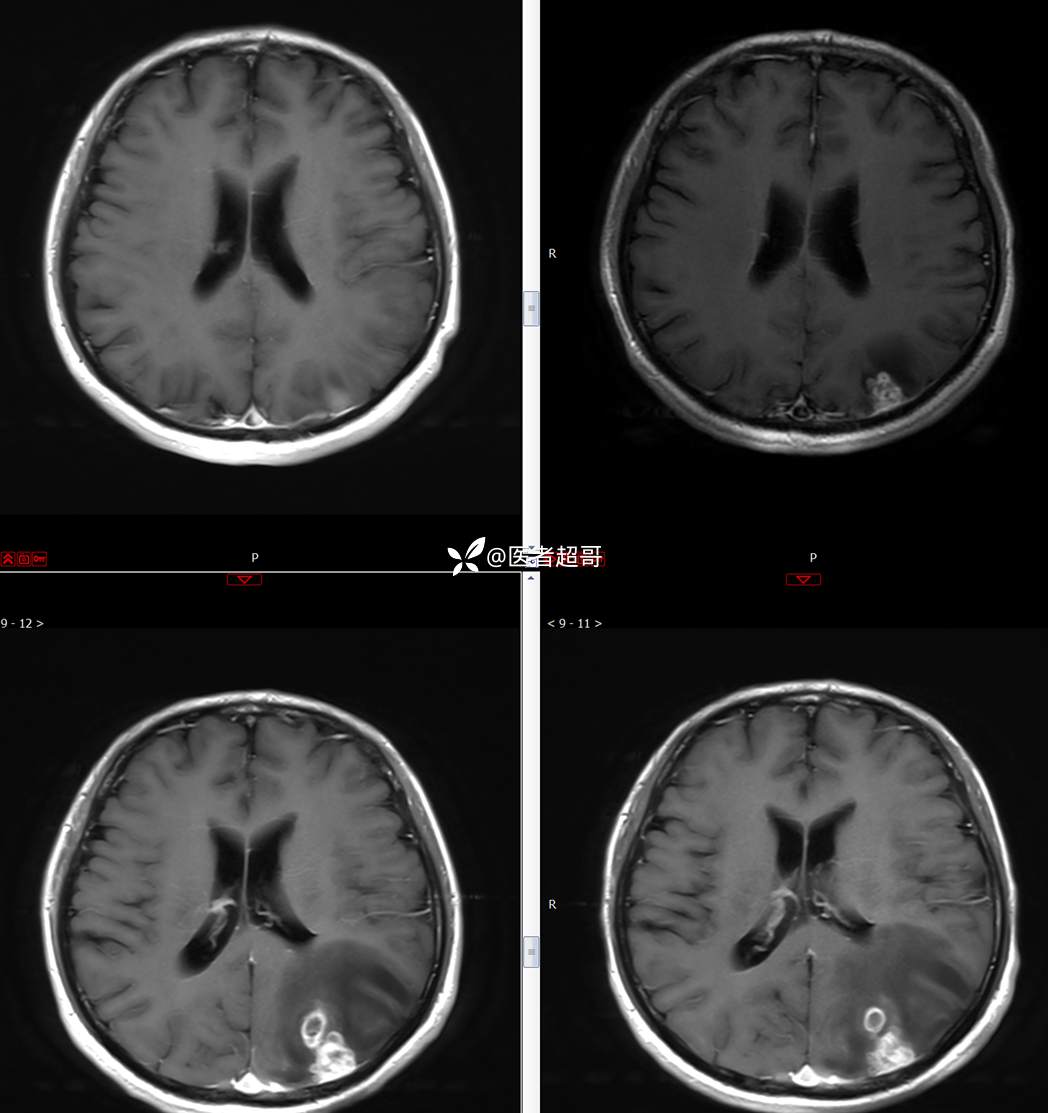

【影诊笔记773】头痛、头晕10天,CT、MRI齐全,请高诊!

主 诉:头痛、头晕10天

现病史:患者10天前无明显诱因感头痛、头晕,伴记忆力减退,无恶心、呕吐,无肢体抽搐及肢体活动不灵等,于我院就诊,行颅脑MR示颅内多发占位,现患者为求进一步治疗于我院就诊,以“颅内占位”收入我科。患者目前神志清,精神可,饮食、睡眠正常,体重无明显变化。

既往史:既往急性肝功能衰竭病史.